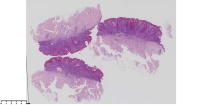

脂溢性角化症?

性别

女

年龄

61岁

一般病史

背部皮肤包块

标本名称

图3

脂溢性角化病